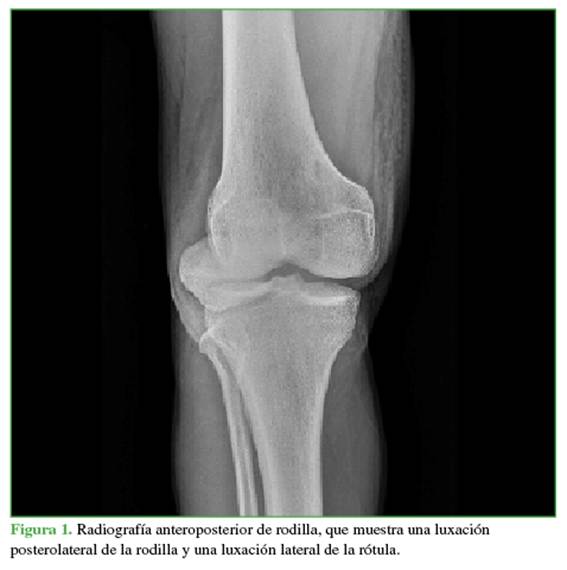

Hombre de 27 años, agricultor y residente en un área rural, sin antecedentes patológicos relevantes. Sufre un accidente de tránsito al caer por un abismo mientras conducía una motocicleta, lo que le provoca un traumatismo en el hombro y la rodilla derechos. Consultó inicialmente en hospital rural, donde le detectaron un gran edema, equimosis y signo del hoyuelo positivo en la rodilla derecha. También, tenía limitación en los arcos de movilidad del hombro y la rodilla. Como no disponían de rayos X, fue derivado a un hospital con servicio de ortopedia. Allí se le tomaron radiografías iniciales (Figuras 1 y 2) y se documentó una fractura diafisaria de húmero que fue inmovilizada con una férula en pinza de azúcar. Además, se diagnosticó una luxación posterolateral de la rodilla y una luxación lateral de la rótula. Dos ortopedistas realizaron tres intentos de reducción bajo sedación (no contaban con anestesia), y lograron reducir la rótula, pero no la rodilla. Se decidió que el paciente requería un centro de trauma para una reducción abierta urgente y descartar una lesión vascular asociada. Se inmovilizó la rodilla con una férula inguinopédica bivalva y fue derivado.